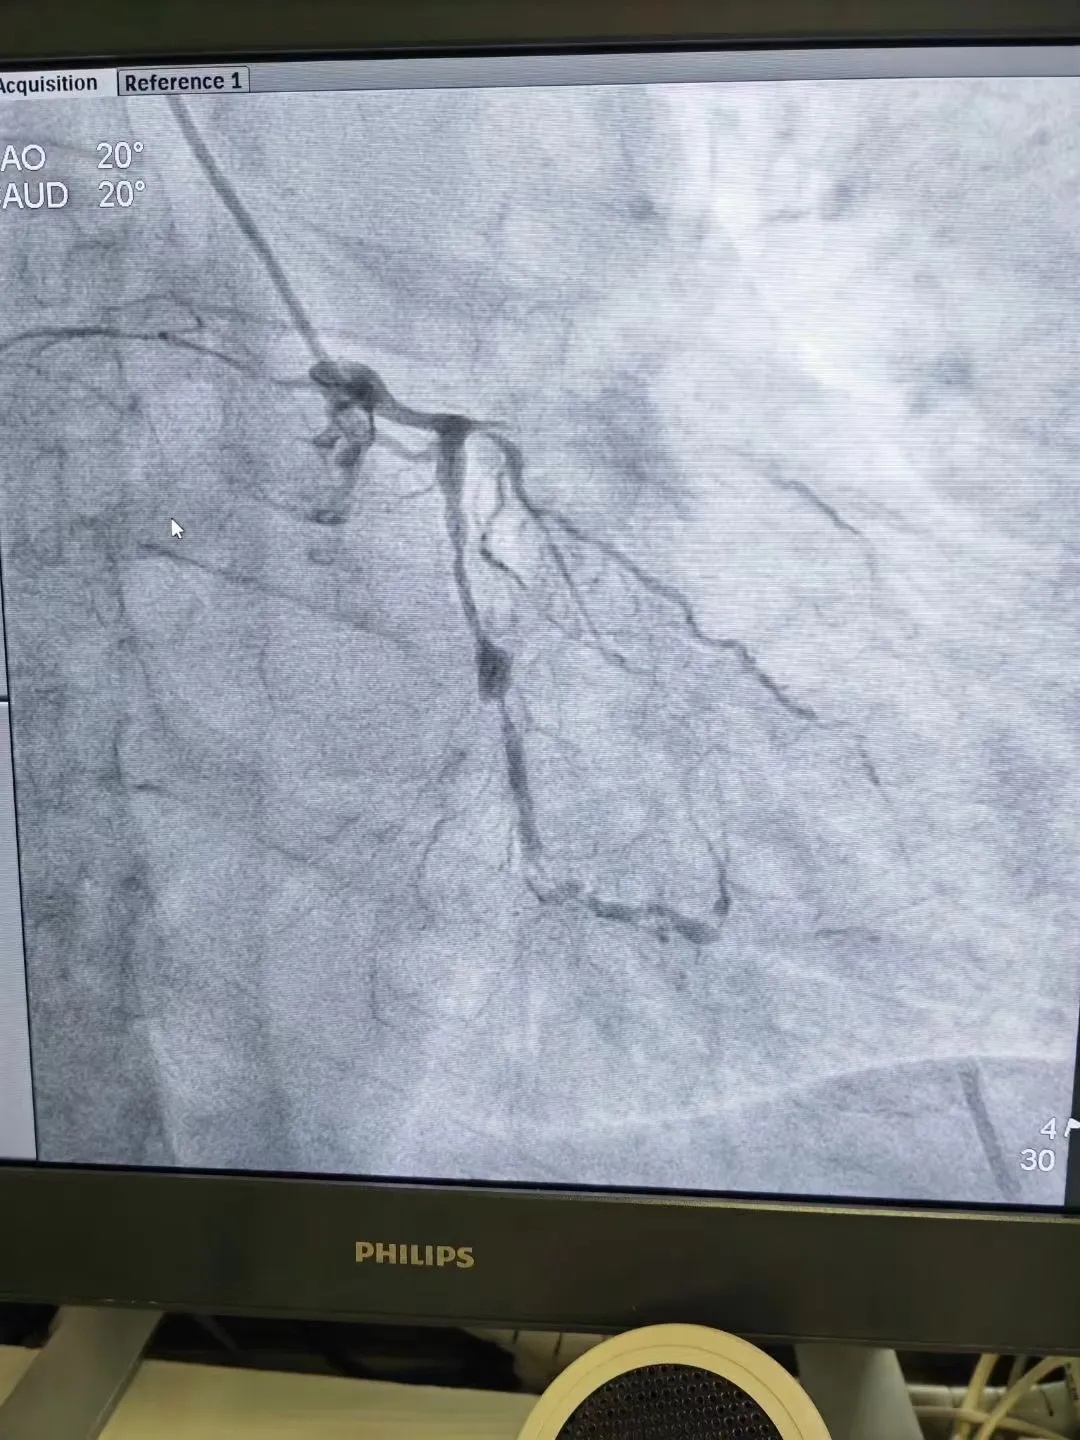

心电图提示徐某有窦性心律,下壁、前间壁、前壁异常Q波,T波改变,血浆心肌钙蛋白偏高。经心内科会诊后,诊断考虑为:急性下壁心肌梗死+冠状动脉粥样硬化性心脏病。

“唉,年纪轻轻血管就变得这样糟糕。熬夜、搓麻将、吸二手烟、生活不规律、血脂高,这些不良习惯都是导致冠心病的因素。”刘主任说,在给徐某右冠近段植入支架后,病情变得稳定,目前已经出院。